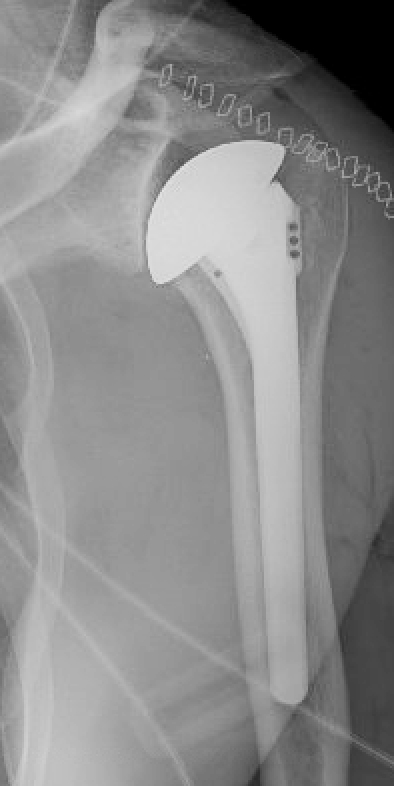

For these reasons, these patients often consider a ream and run procedure which avoids the risks and limitations of a plastic glenoid component (see this link and this link).

Here is a current example of a 40 year old aspiring triathlete who presented with pain and stiffness of the left shoulder after a prior labral repair surgery. On examination his range of motion was as shown below.